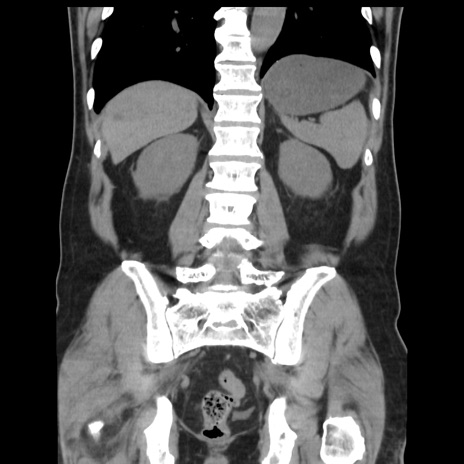

症例16(冠状断像)

【現病歴】 約1ヶ月前より間欠的に腹痛と嘔吐あり、当院消化器内科を受診したところCTで多発する肝臓のLDAを指摘され、精査中であった。以降は消化器症状は安定していたが、2日前より嘔気と腹痛があり、同日より排便・排ガスが消失した。改善認めず、 本日、救急外来を受診した。